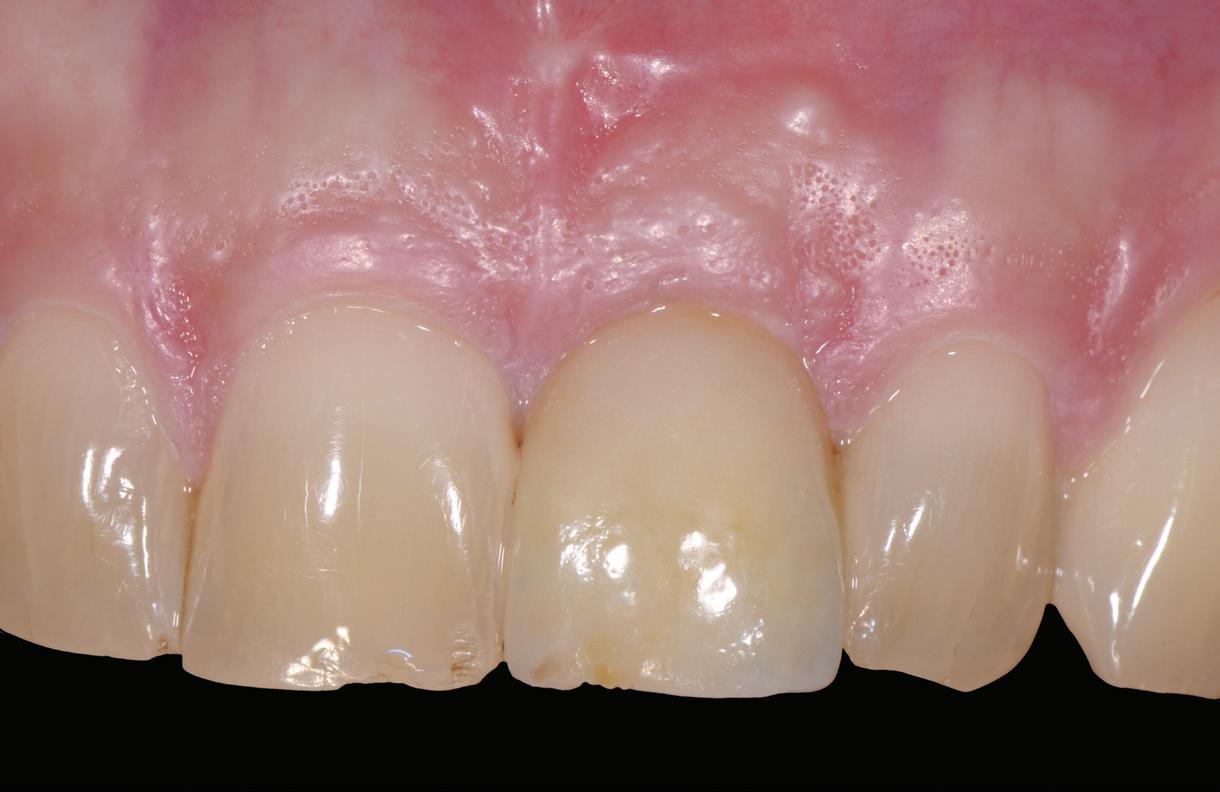

SITE AUGMENTATION Reconstituirea țesutului moale periimplantar și papilar în zona estetică

RECONSTITUIREA țesuturilor moi periimplantare. Scopul acestui raport de caz este de a demonstra procedurile chirurgicale utilizate pentru corectarea unui defect al țesuturilor moi periimplantare folosind țesutul moale interdentar în combinație cu tuberozitatea ca locație donatoare de țesut conjunctiv, utilizând o abordare prin tunelizare într-o zonă estetică.

Totuși, ca și în cazul implanturilor de titan, în rare cazuri, și la cele ceramice poate apărea o recesie nedorită cu expunerea umărului implantar. Cu toate acestea, din punct de vedere estetic, această recesie a gingiei inflamate este posibil să fie mult mai bine tolerată de către pacienții preocupați de marginile întunecate ale implanturilor de titan (fig. 2).

Trebuie remarcat, totuși, că în cazul implanturilor ceramice, ca și în al celor de titan, cementita, adică inflamația periimplantară cauzată de reziduurile de ciment, poate duce la periimplantită. În plus, la implanturile din dioxid de zirconiu poate apărea supraîncălzirea la înșurubarea implantului în os, iar suprafețele excesiv de aspre sau poroase ale implantului pot cauza defecte osoase periimplantare din cauza termoconductivității reduse a materialului. Deși sunt necesare mai multe dovezi științifice care să demonstreze o tendință mai scăzută spre periimplantită în cazul implanturilor ceramice, argumentul esențial pentru aceste implanturi bazat pe experiența clinică este starea excelentă și aproape constant lipsită de inflamație a țesuturilor moi periimplantare (fig. 3).